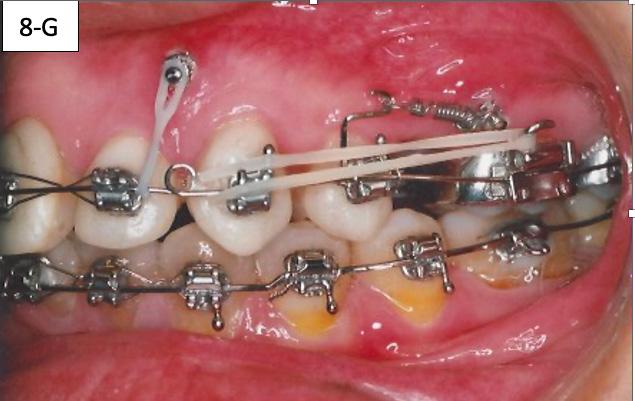

The brackets were bonded on maxillary cuspids, bicuspids and mandibular anterior teeth followed by placement of a 014 SS sectional wire in the maxilla and a .014 SS arch wire in the mandible. Maxillary second bicuspids were extracted, and a 1.6 x 8.0 mm AncorPro (OrthoOrganizers) TADs were inserted just mesially to the first molars. Closing coil springs were attached from the TADs to the first bicuspids (Regional Acceleratory Phenomenon) (Figure 8-A, B, C).7

The brackets were bonded on the maxillary incisors and there was a progression of the arch wires a .014 NiTi, a .016 SS and a .018 SS. The progression of the arch wires in the mandible was a .016 NiTi, a .016 SS, a .018 SS and a .018 x 025 SS with the step-down distally to the cuspids. A 1.6 x 8.0 mm Ancor Pro TADs were inserted on the buccal aspect distally to the maxillary lateral incisors to aid the intrusion of the maxillary anterior sextant.8 Maxillary incisors were laced back, to prevent splaying during the intrusion and two links of an elastomeric chain were attached from the TADs to the arch wire. Power arms were bent from a .016 x 022 SS wire and ligature tied to the bracket #13(6) an #24(12).

Closing coil springs were attached from TADs to the power arms. To prevent an undesirable labial moment (flaring) of the maxillary incisors, Class I (labial intra) elastics (¼” – 4.5 oz) were

placed from the buccal hook of the maxillary first molar to the helical loop on the arch wire. The helical loop was fabricated just distally to the maxillary lateral incisors on a. 018 SS arch wire (Figure 8-D, E, F, G).

FIG. 8A: Odontectomy of #15(4) & # 25(13)

FIG. 8B: CCS and TAD, right lateral view

FIG. 8C: CCS and TAD, left lateral view

FIG. 8D: TADs inserted, frontal view

FIG. 8E: TADs in situ, radiogram

FIG. 8F: Class I elastic, right lateral view

FIG. 8G: FClass I elastic, left lateral view